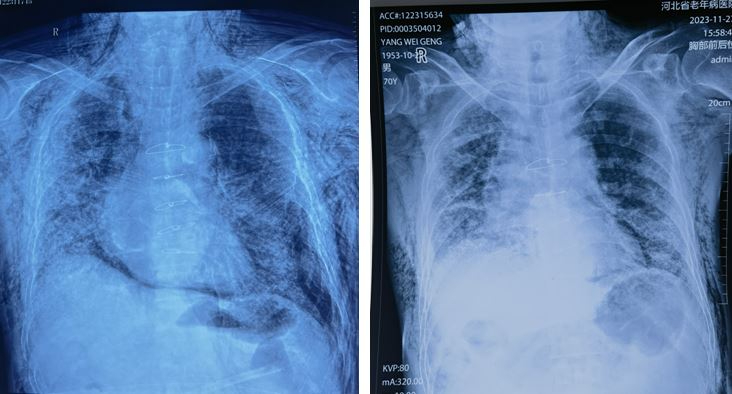

影像学检查,左为入院时,右为入院两周后

入院第4天,杨先生出现颜面部肿胀明显,双上臂、胸部、颈部、背部不同程度气肿,触之有握雪感,推之有气体流动。进行影像学检查,结果显示双侧气胸,皮下及纵膈内气肿,双肺肺间质纤维化,随时有呼吸骤停风险。

10天后,杨先生颜面部肿胀、双上肢、前胸、背部皮下气肿明显好转。复查影像学检查,结果显示气胸范围明显变小,皮下及纵膈内气肿明显好转。